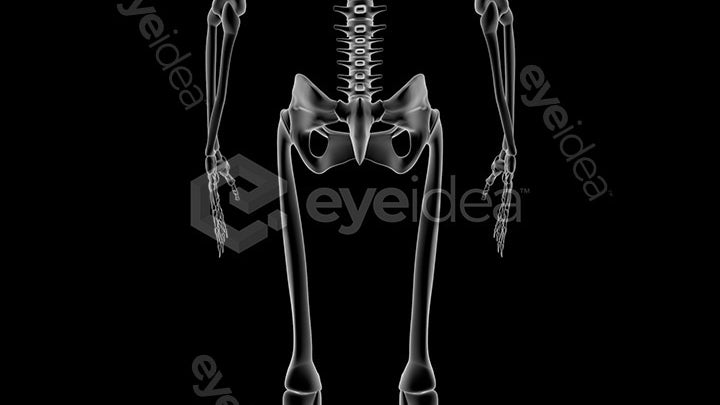

Our Stock-Packs™ are curated to include a varied

range of angles, motion, styles and formats,

ensuring that creators can find the assets

they want fast and easy.

Our stock videos, images, and animations come

with a wealth of experience spanning over two

decades, giving creators assurance

of premium quality assets.